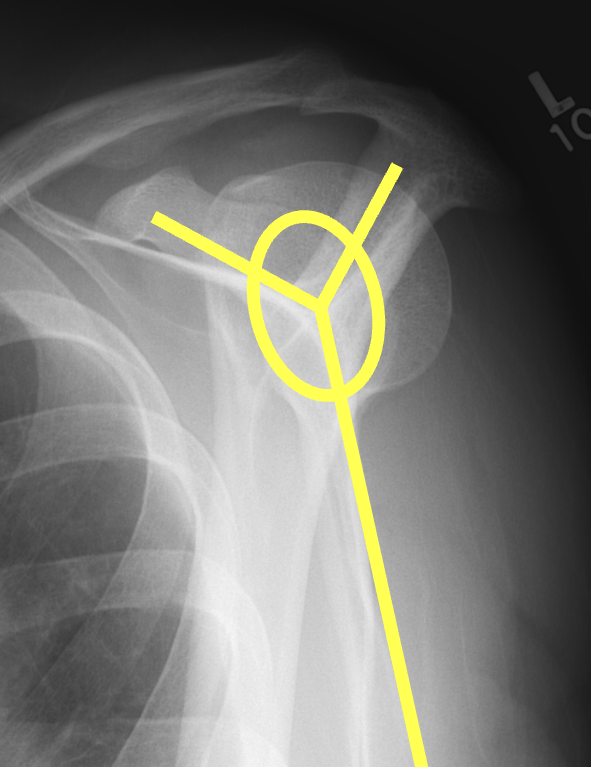

Scapular lateral

Center of the humeral head must be centered on the Y / Mercedes sign

Y is formed by

- coracoid anteriorly

- scapular spine posteriorly

- scapula body inferiorly

Posterior shoulder dislocation

Posterior shoulder dislocations